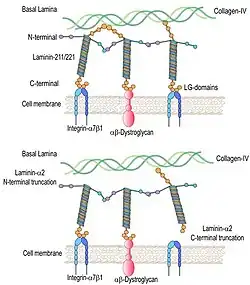

There is no definite cure available for LAMA2-MD. However, preclinical studies on experimental animal models of Laminin alpha-2 chain deficient congenital muscular dystrophy are showing favorable yet early results. Generally, these preclinical studies are geared toward investigating the various factors behind disease initiation and progression, and exploration of potential ameliorating or curative therapies.[24] Preclinical studies focus on combating substances that regulate and promote muscle fibrosis in the pathogenesis of LAMA2-MD e.g., TGF-β. This may reduce muscle fibrosis and enhance healthy muscle architecture subsequently.[25][26][27] Alternatively, preclinical studies can be geared toward enhancing proteins that are involved in muscle regeneration. Laminin alpha2 (Laminin-211) and laminin-221 complex are an important molecule for muscle cell receptors namely integrin-α7β1 and α-dystroglycan. In LAMA2-CMD the laminin alpha2 deficiency results in malfunctioning or down regulation of integrin-α7β1 and α-dystroglycan. This disrupts the proper linkage between the basal lamina and muscle cell membrane. Consequently, the contractile mechanism is disrupted. Integrin-α7β1 is important to satellite cell function, and myoblast adhesion and viability. Thusly, integrin-α7β1is an important contributor to skeletal muscle regeneration. Cell therapies that compensate for the deficiency or down regulation of integrin-α7β1 have the potential to delay or control the muscle degenerative process and preserve muscle architecture in LAMA2-CMD patients. Additionally, the use of laminin-111 treatment in experimental mouse models of LAMA2-CMD has showed satisfactory results in terms of increase in life expectancy muscle function and regeneration.[28]